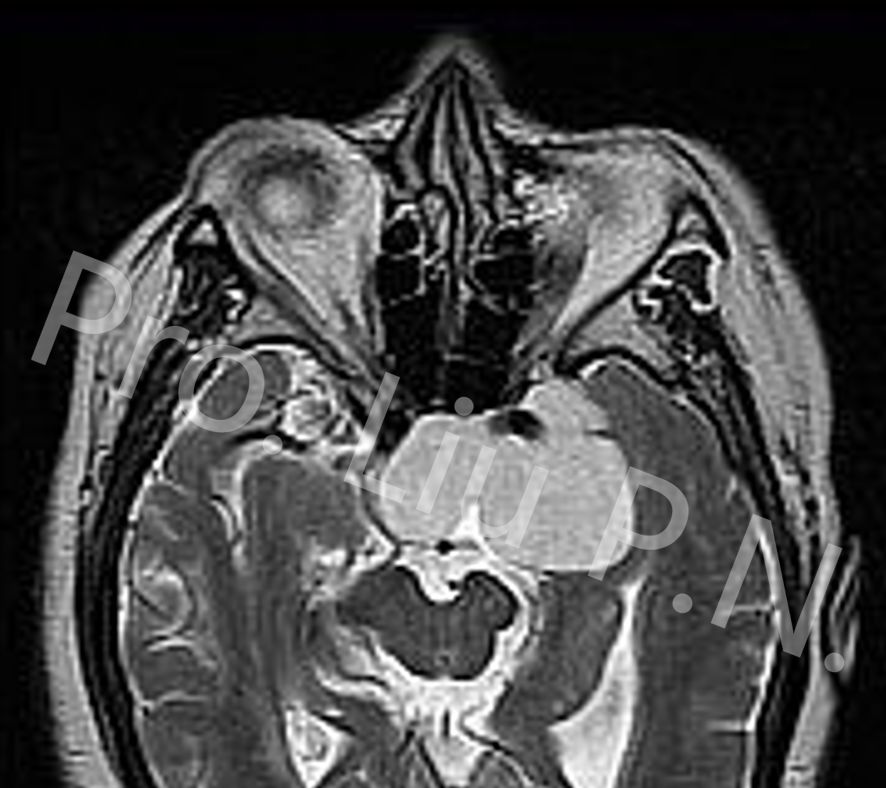

三、不同海绵窦区肿瘤影像特点

![]()

1. 海绵窦内海绵状血管瘤

2. 海绵窦内神经鞘瘤

3. 海绵窦内表皮样囊肿

4. 侵袭海绵窦垂体瘤

5. 海绵窦脑膜瘤

6. 左海绵窦皮样囊肿

7. 海绵窦内神经母细胞瘤

8. 海绵窦内血管外皮细胞瘤